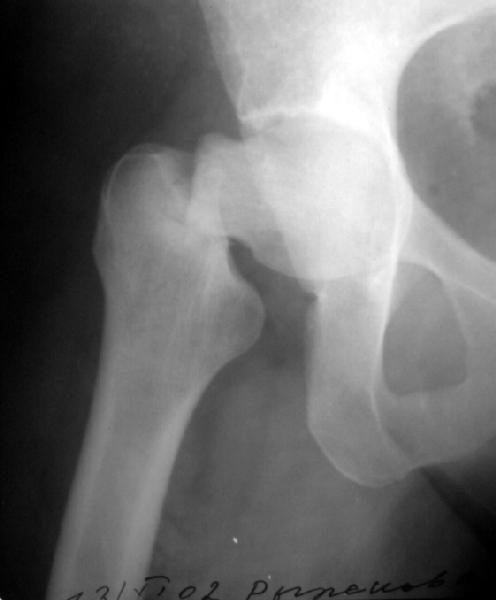

To me the whole head, neck and adjacent acetabular area look sclerotic.

Do you have x-ray of the whole pelvis with both hips for comparison of areas. Also like James carr suggested a metabolic work up.

This one was made at the initial hospital two days before transfer.

Прилагаю еще одну рентгенограмму - обзорный снимок таза от 11 ноября, еще до перевода к нам. Ранее были посланы снимки, сделанные 13 ноября

уже у нас.

Думаю прежний снимок мало что меняет. Есть базо-цервикальный перелом, на мой взгляд, несвежий. Снимок 11.11.02 технически хуже 13.11.02 и сделан в несколько иной проекции. Жаль что в обеих случаях нет аксиального снимка шейки, на мой взгляд просто необходимого для диагноза.